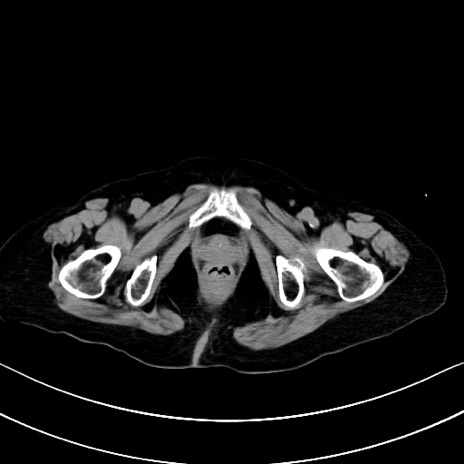

横断像

他院CT